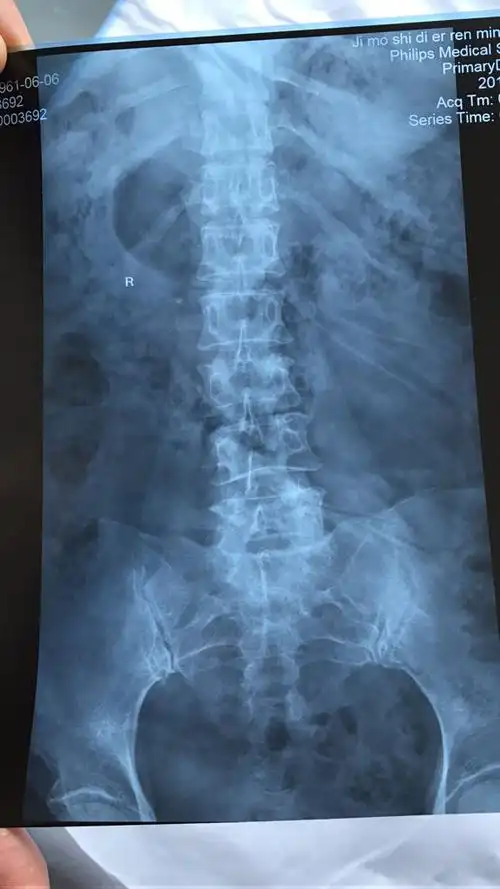

老年人腰椎压缩性骨折,行腰椎锥体球囊扩张术,术后症状缓解 - 好大夫

术前x线平片示腰2椎体明显压缩骨折,压缩约1/2.

老年患者腰椎压缩性骨折微创椎体球囊扩张